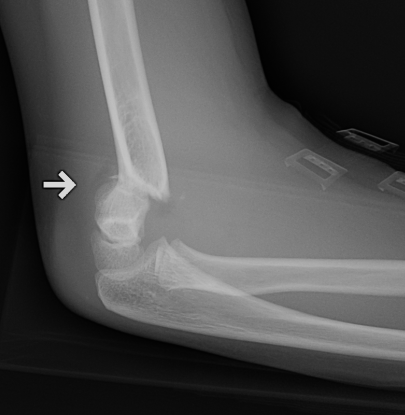

AP X-ray

Baumann's Angle

Technique

- angle between longitudinal axis humerus and capitellar physis

- should equal uninjured side

- 75o normal

Cubitus varus

- varus malposition > 81°

Cubitus valgus

- < 70o